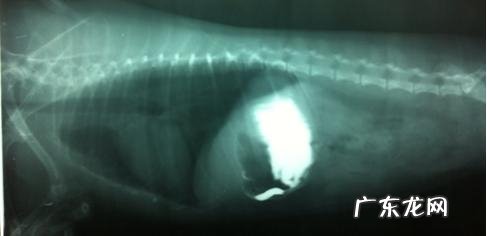

x光图

灌服钡餐15个钟头以后,右边位,钡餐在胃内残余一部分,剩下来到乙状结肠位置,一切正常状况在灌服钡餐15个小时后,都把乙状结肠一部分走完或是是到十二指肠 。可基础判断在乙状结肠位置产生堵塞,使钡餐不可以流到肠道后段 。